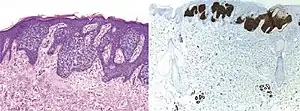

Comparison H&E stain (left) with BerEP4 immunohistochemistry staining (right) on a pathological section having BCC with squamous cell metaplasia. Only BCC cells are stained with BerEP4.[1]

Comparison H&E stain (left) with BerEP4 immunohistochemistry staining (right) on superficial BCC pathological sections mimicking Bowen’s Disease.[1] At bottom, columnar epithelium in normal sweat glands stain positive too.

BerEp4 (also Ber-EP4) is a histologic stain mainly used to aid in the diagnosis of basal cell carcinoma (BCC).[2] It is an antibody to EpCAM (epithelial cell adhesion molecule).[1]

BerEp4 has a high sensitivity and specificity in being positive only in BCC cells.[1] BerEp4 is normally negative in squamous epithelium and mesothelium, but otherwise normally positive most epithelial cells of the body.[3] It can also help in distinguishing pulmonary adenocarcinoma (positive BerEp4) from mesothelioma (generally negative BerEp4).[3][4]